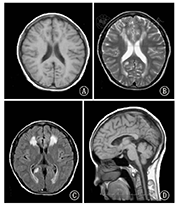

例1,男,初次于北京大学第一医院就诊年龄为9岁。就诊时主要表现:(1)肢体无力。患儿7岁时在感染后10 d出现左下肢无力跛行,5个月后出现右下肢无力,随后出现左手活动不灵,逐渐加重发展至不能独走及独站。(2)躯干肌无力及呼吸肌无力。从平卧位不能自行坐起,不能翻身;呼吸浅促,活动后明显。(3)吞咽困难、饮水呛咳、语音低弱、语速慢,呈进行性加重。(4)尿便障碍。排尿前需等待7~8 min,大便每2~3 d 1次伴粪便干结。(5)阵发性头晕,伴恶心呕吐及困倦。以上症状在整个病程中有波动,感染后加重,感染控制后不能恢复至感染前状态,为进行性加重。就诊时查体:头围54.5 cm,下颌反射(+),微笑时口角右斜,咽反射存在,伸舌左偏。双上肢肌力Ⅳ级,双下肢肌力Ⅲ级,肌张力增高。双侧肱二、三头肌腱反射活跃,双侧膝腱反射亢进,双侧踝阵挛阳性。双侧Hoffmann征(-),双侧Babinski征(+)。既往史:围生期(-),3个月抬头,6个月独坐,1岁说简单话,1.5岁独走,发病前发育基本同同龄儿;4岁时发热抽搐1次,表现为双眼睑眨动,口唇发绀,双上肢屈曲强直,持续时间不详。家族史(-)。末次随访时患儿10岁,四肢痉挛性瘫痪,仍不能独站,可独坐,但坐立时间较短,易疲劳;认知无倒退,吞咽困难、饮水呛咳等表现消失;出现癫痫持续状态1次,不伴发热,表现为睡眠中突然出现双眼上翻、呼之不应,持续约1 h。头颅MRI示前头部皮层下白质、双侧脑室后角旁白质对称性T1加权像(T1WI)低、T2加权像(T2WI)高、T2液体衰减反转恢复序列(T2FLAIR)高信号;7~9岁无明显进展,双侧基底核T2WI及T2FLAIR像信号稍高,延髓可见T2WI高信号,8岁以后更加明显(图1)。GFAP基因测序发现已报道的新生杂合错义突变c.1073C>T(p.Ala358Val)。

注:A~D为7岁时头颅MRI;E~H为8岁时MRI;I~L为9岁时MRI;A、E、I为T1加权像;B、F、J、D、H、L为T2加权像;C、G、K为T2液体衰减反转恢复序列图像 A-D: the brain MRI of patient 1 at 7 years old;E-H:at 8 years old;I-L:at 9 years old;A,E,I:pictures of T1 weighted imaging;B,F,J,D,H,L:T2 weighted imaging;C,G,K:T2 fluid attenuated inversion recovery imaging